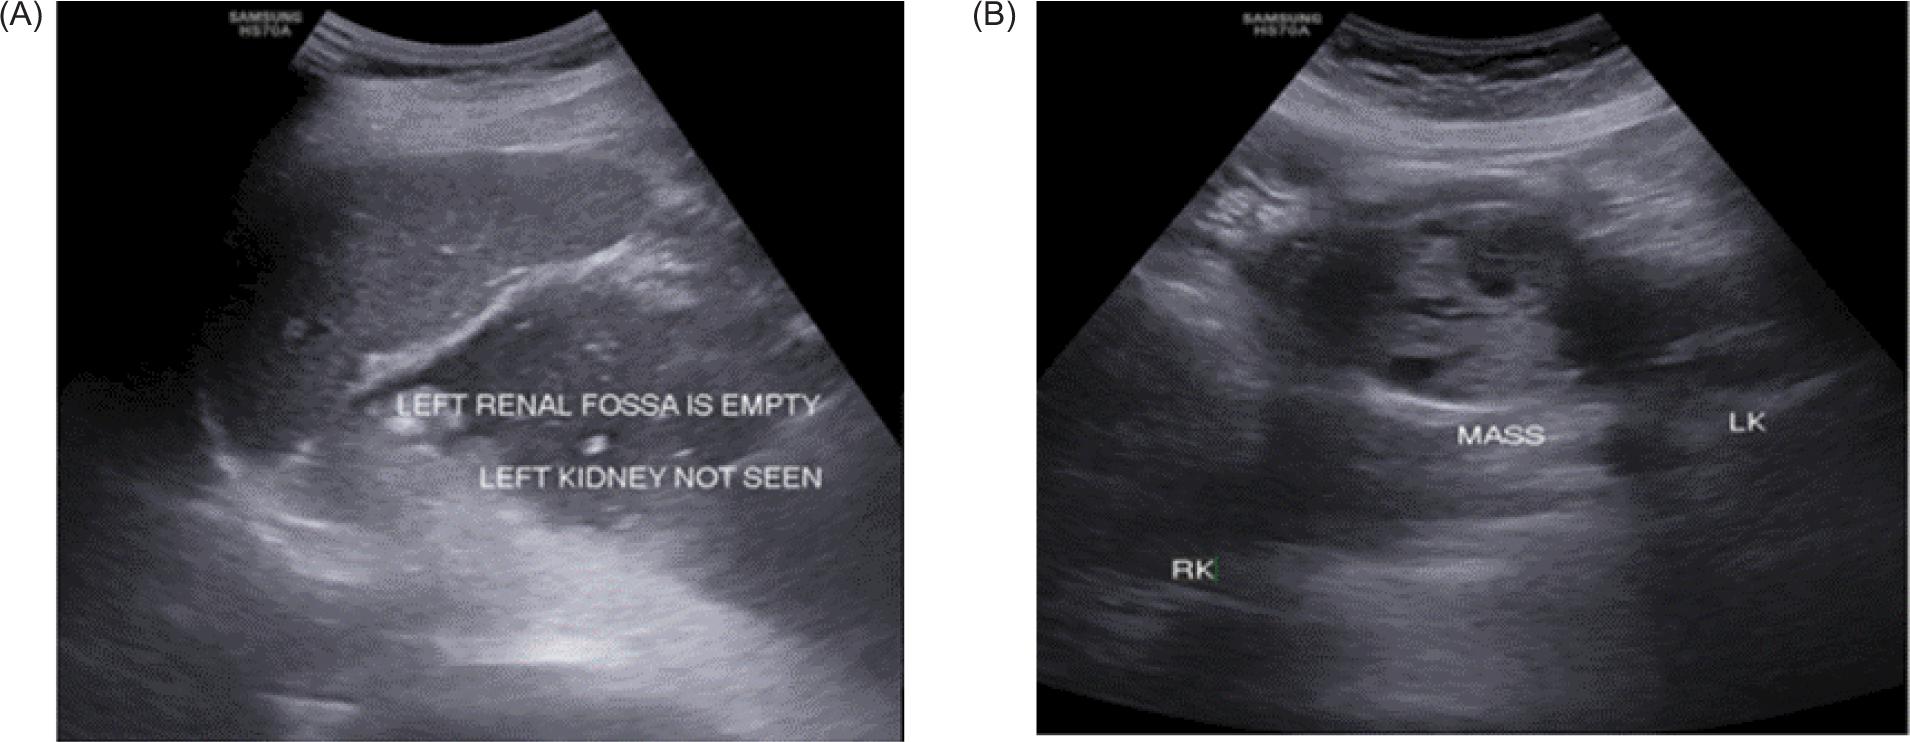

Furthermore, the patient was subjected to CT renal angiography which revealed one main renal artery showing hilar branching supplying right upper and interpolar region, and right accessory renal artery supplying interpolar and lower polar region. Left main renal artery showed hilar branching supplying the left interpolar and lower polar region. Out of the two left renal accessory arteries, one artery supplied the left interpolar and lower polar region and the other artery supplied the left upper pole. Another artery arising from infra renal abdominal aorta on the right side at the level of third lumbar vertebra trifurcated the medial branch that supplied isthmus, middle branch that supplied tumor, and lateral branch that supplied the right kidney (Figure 5). Patient could not afford PET-CT, and TNM staging revealed PT1bN0M0 Stage 1.

Figure 5: Three-dimensional volume rendering CT angiography showing renal and accessory arteries on either sides supplying both kidneys. Another artery arising from infra renal aorta supplying isthmus, tumor, and adjoining lower pole of right kidney.